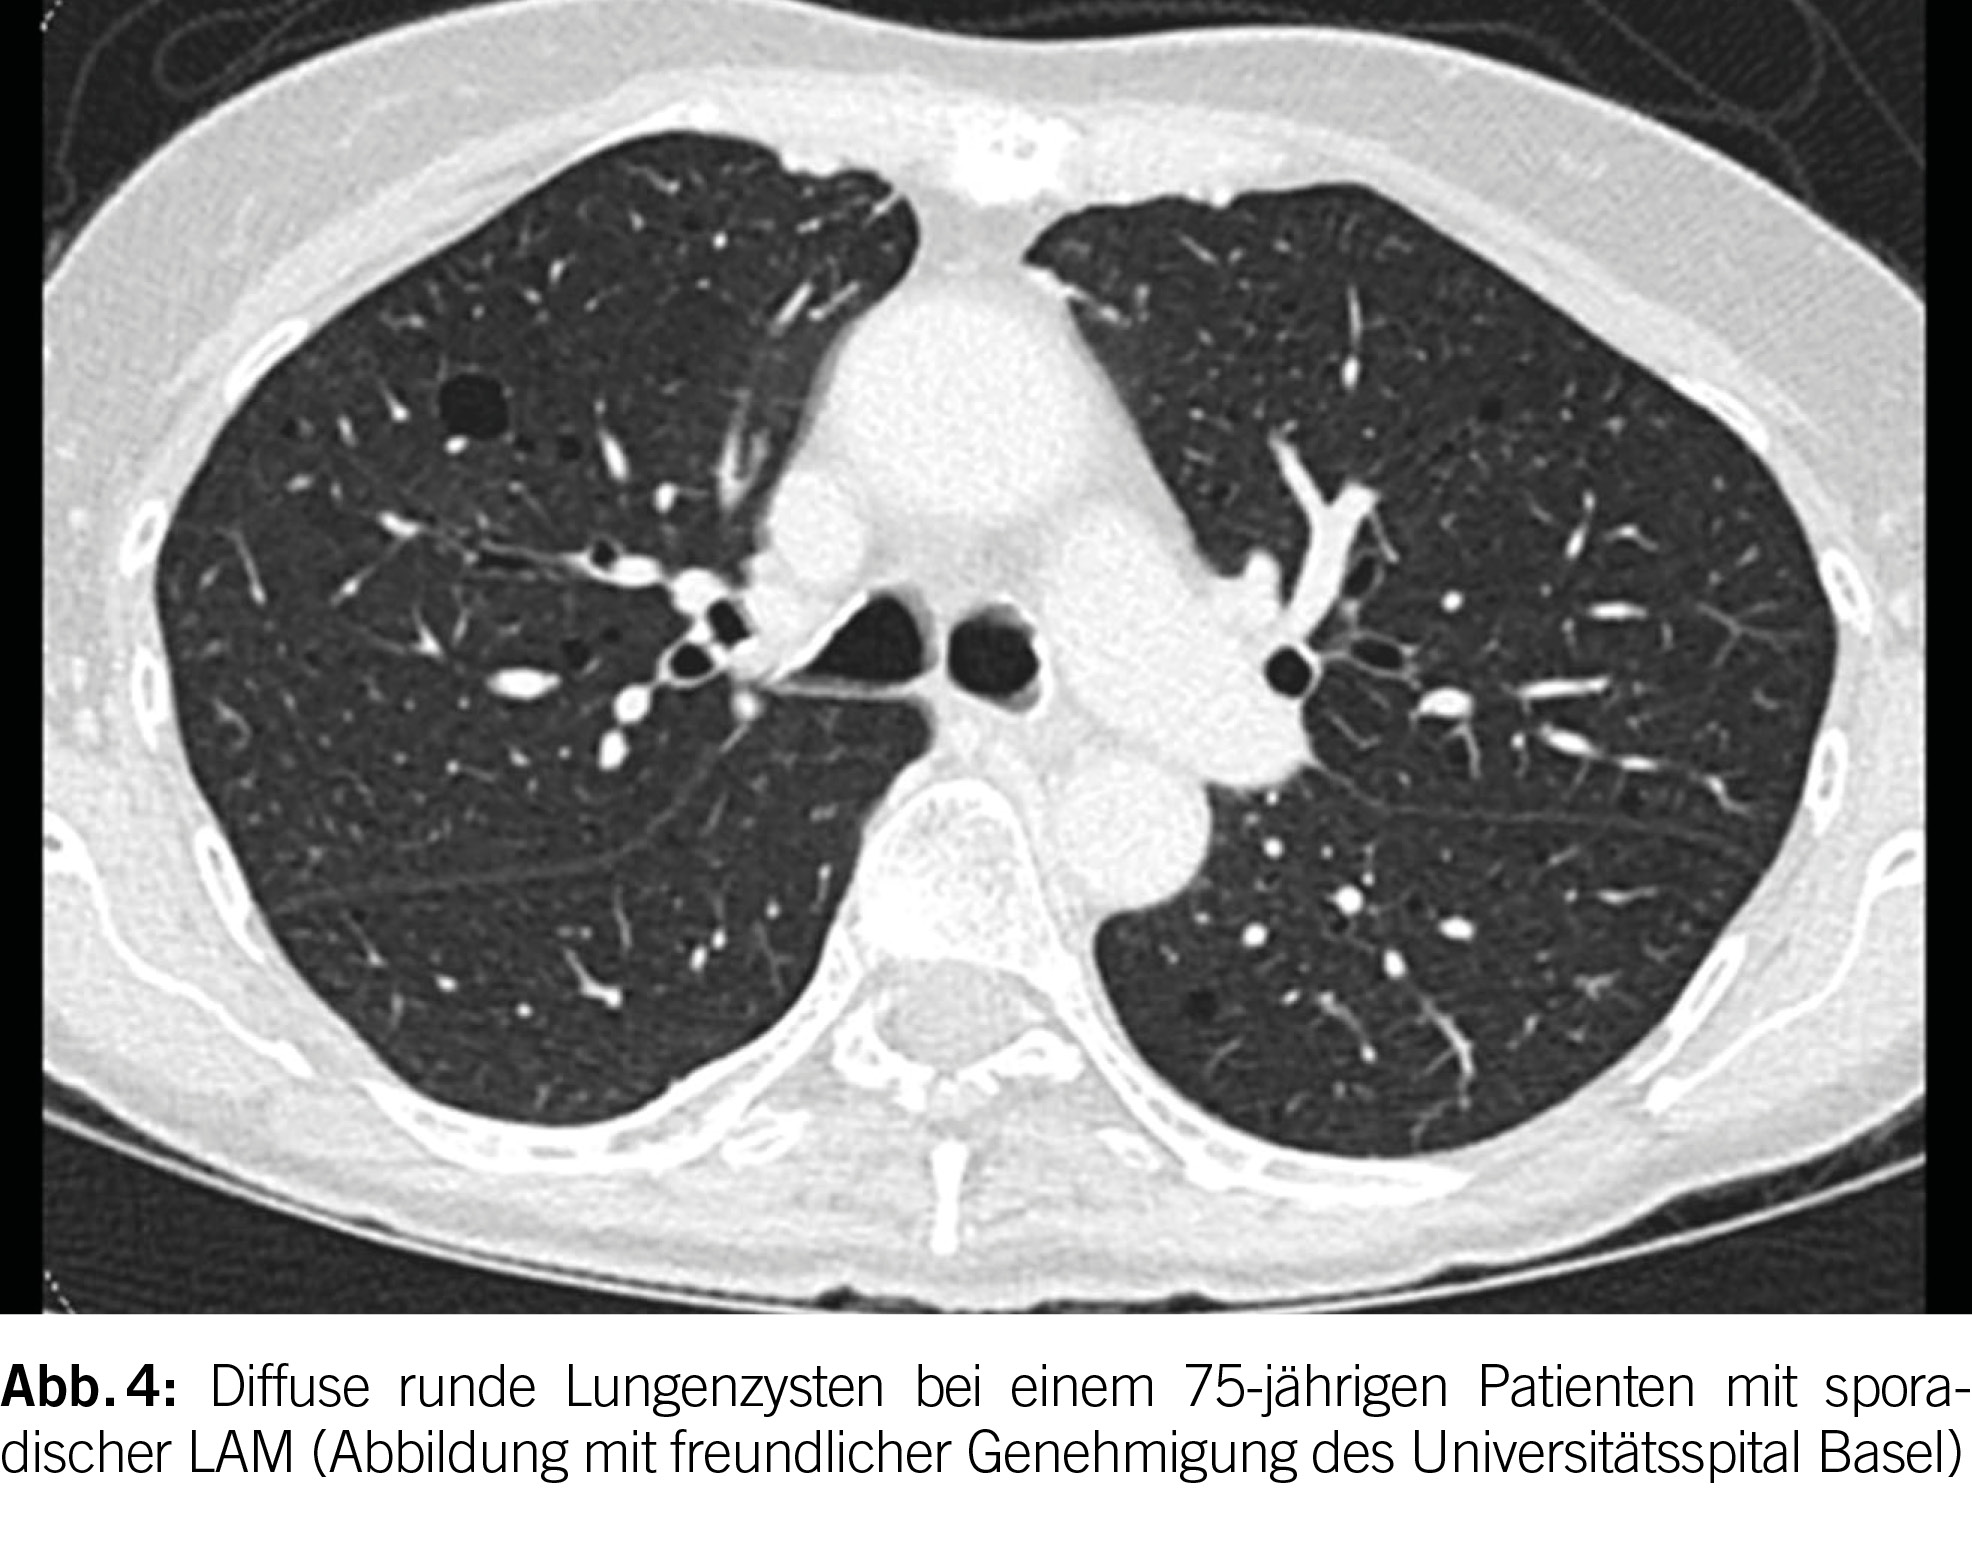

Lungenzysten bei LAM sind typischerweise rund, gleichmäßig in beiden Lungen verteilt und in Form und Grösse relativ einheitlich (Abbildung 4). Bei TSC-LAM treten häufig Lungennoduli mit einer Grösse von 2 bis 14 mm auf, die die zystischen Läsionen begleiten und eine multifokale mikronoduläre Pneumozyten-Hyperplasie repräsentieren. Bei 10% der LAM-Patienten treten weiterhin chylöse Pleuraergüsse auf.